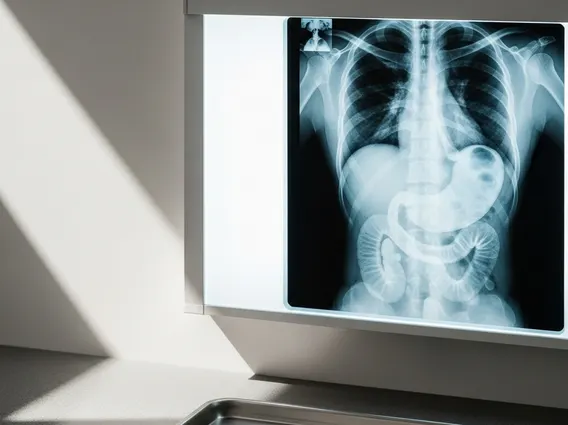

What is an Upper Gi Series refers to a specialized X-ray examination that allows doctors to visualize the upper part of the gastrointestinal (GI) tract. This includes the esophagus, stomach, and the first part of the small intestine, known as the duodenum. During the procedure, the patient drinks a liquid contrast material, typically barium, which coats the lining of these organs, making them visible on X-ray images. This allows radiologists to observe the shape, function, and any abnormalities within these structures.

The procedure is also sometimes referred to as a barium swallow or an esophagram, particularly when the focus is primarily on the esophagus. It provides dynamic images, meaning the radiologist can watch the barium move through the digestive tract in real-time, helping to identify issues with swallowing or the movement of food.